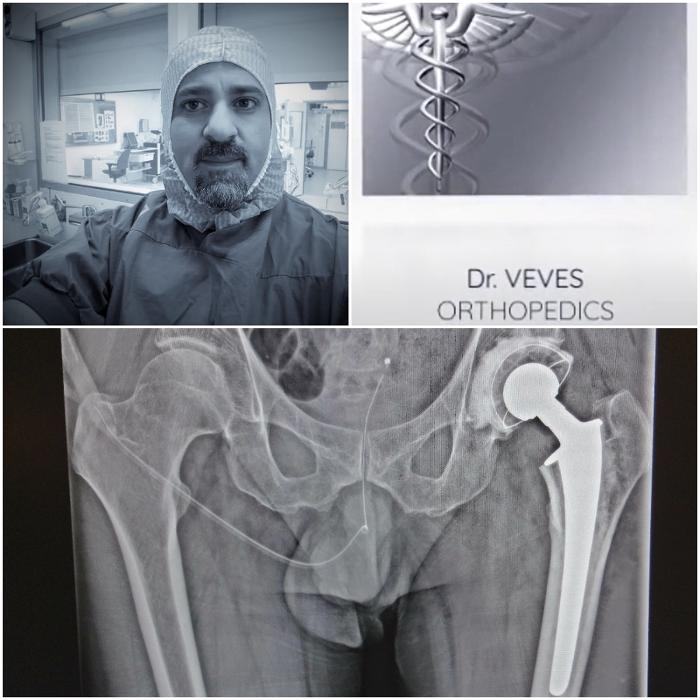

Ορθοπαιδικός Παγκράτι, θεραπεία αρθρίτιδας Παγκράτι, ρήξη μηνίσκου Παγκράτι

ρήξη χιαστού Παγκράτι, ορθοπαιδικό ιατρείο Παγκράτι, ορθοπαιδικός Παγκράτι

Ρήξη μηνίσκου Παγκράτι, ρήξη χιαστού Παγκράτι, ορθοπαιδικό ιατρείο Παγκράτι

Αρθροσκόπηση γόνατος Παγκράτι, Ορθοπαιδικός Παγκράτι, χειρουργός ορθοπαιδικός Παγκράτι, ορθοπαιδικοί ιατροί Παγκράτι, ορθοπαιδικό ιατρείο Παγκράτι

Ρήξη μηνίσκου Παγκράτι, ρήξη χιαστού Παγκράτι, ορθοπαιδικό ιατρείο Παγκράτι